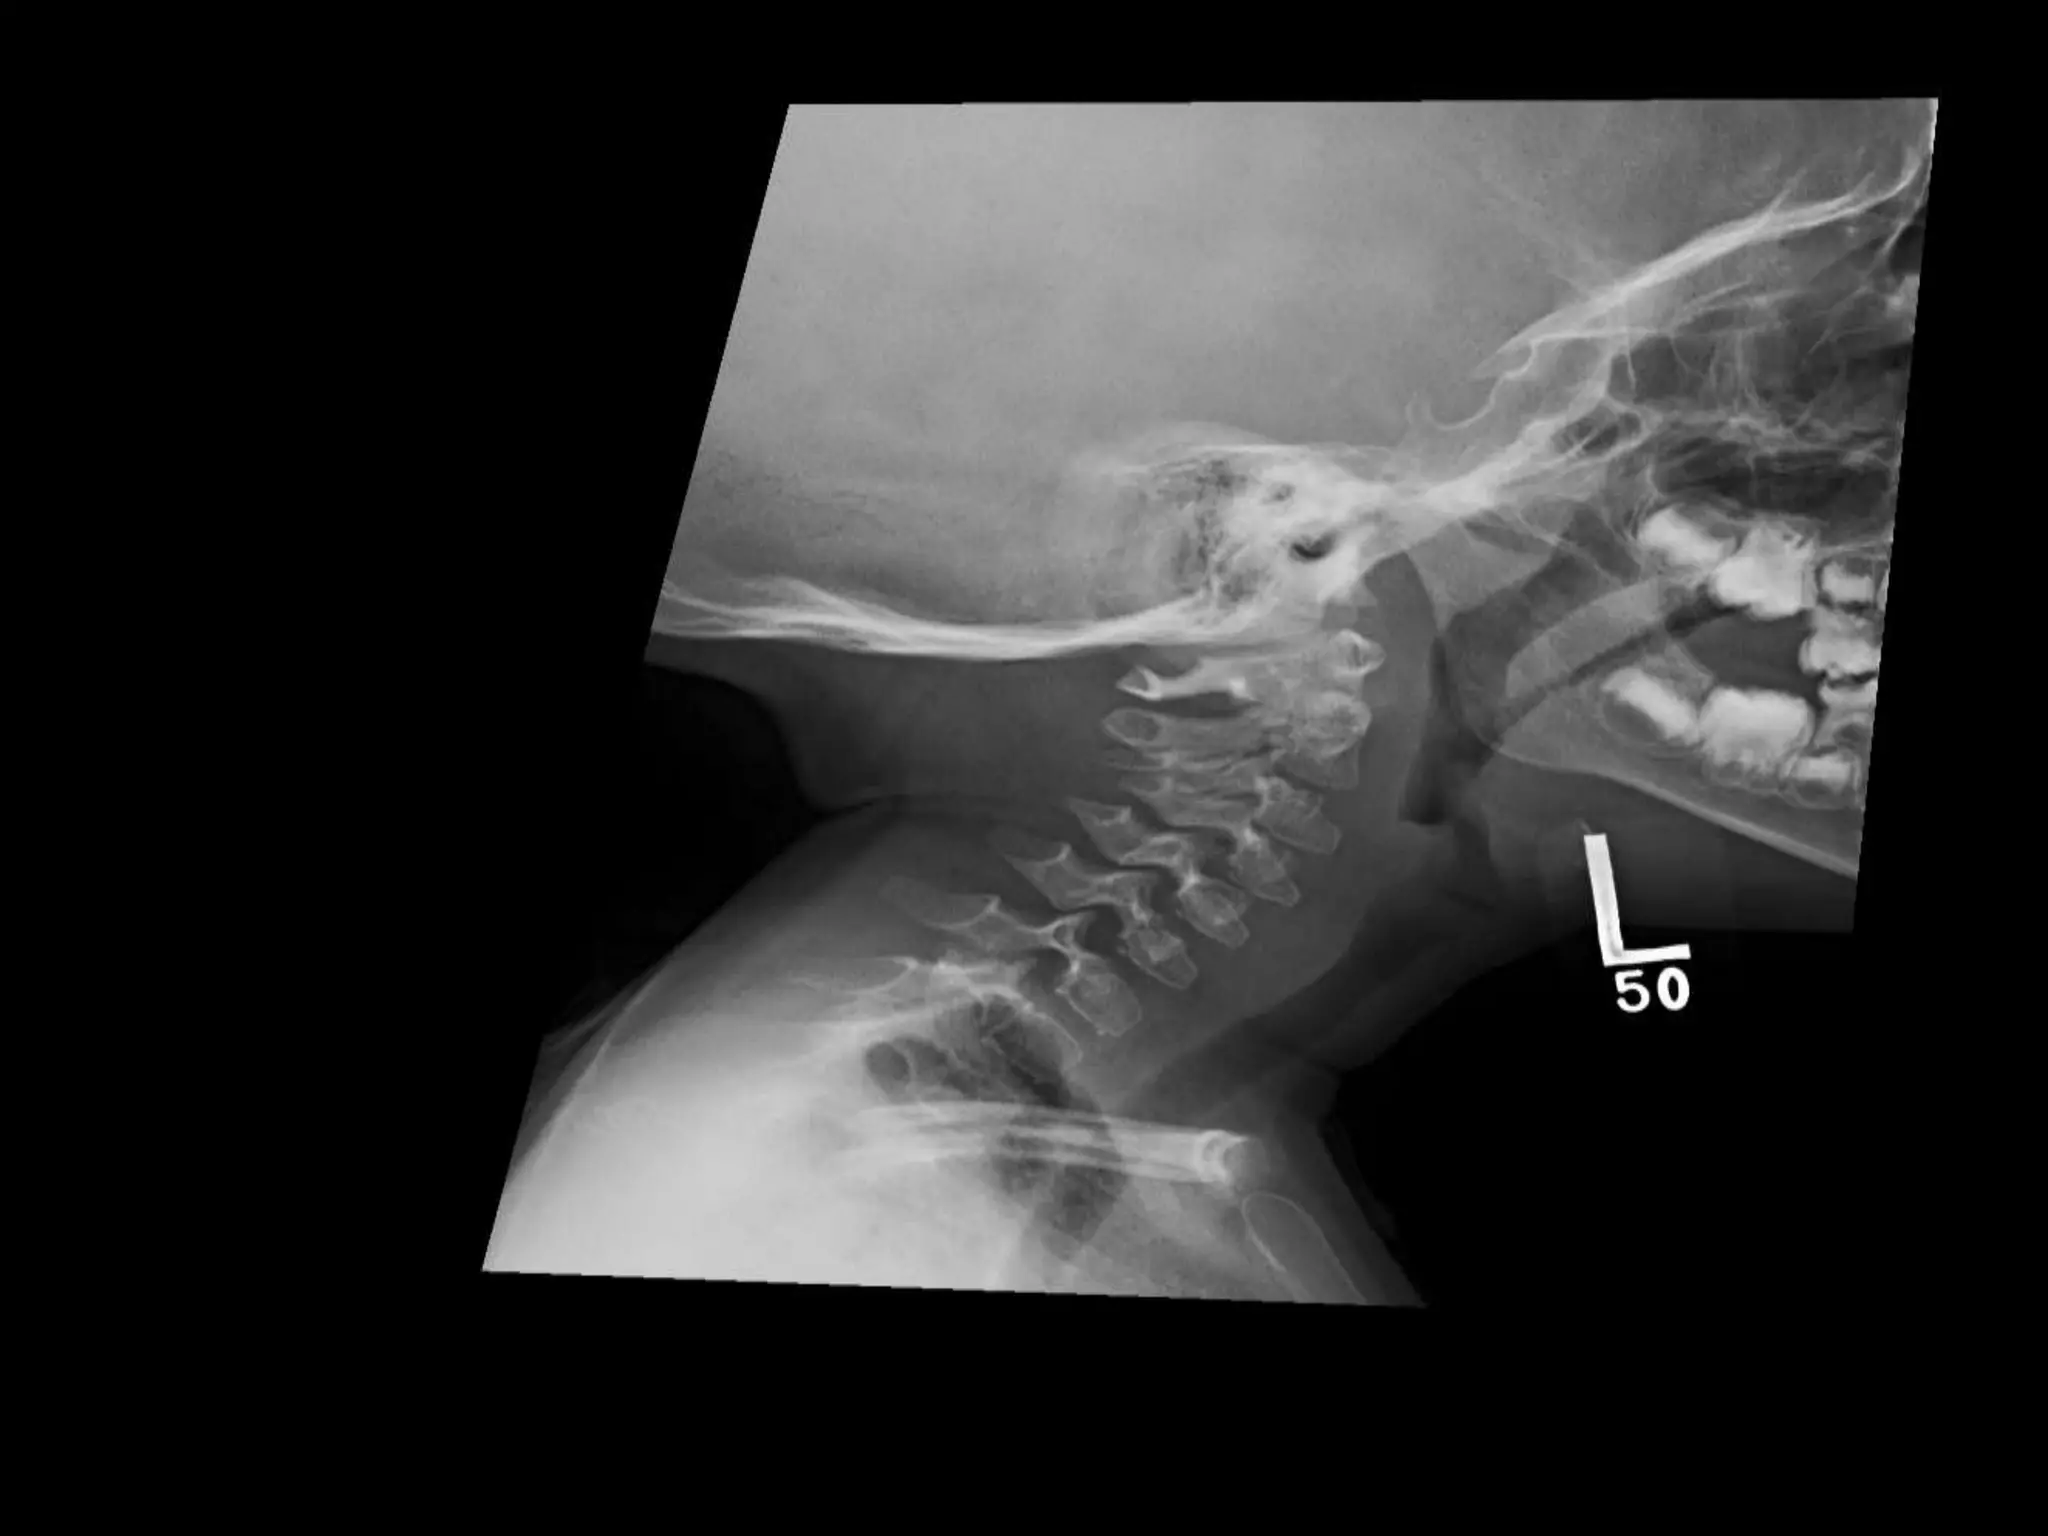

PYKNODYSOSTOSIS

• Short stature

• Frontal bossing

• Mandible underdevelopment

• Abnormal dentition

• X-Ray: skull enlarged with wide sutures/ open

fontanellae

• Facial/mandible hypoplastic --- triangled facies